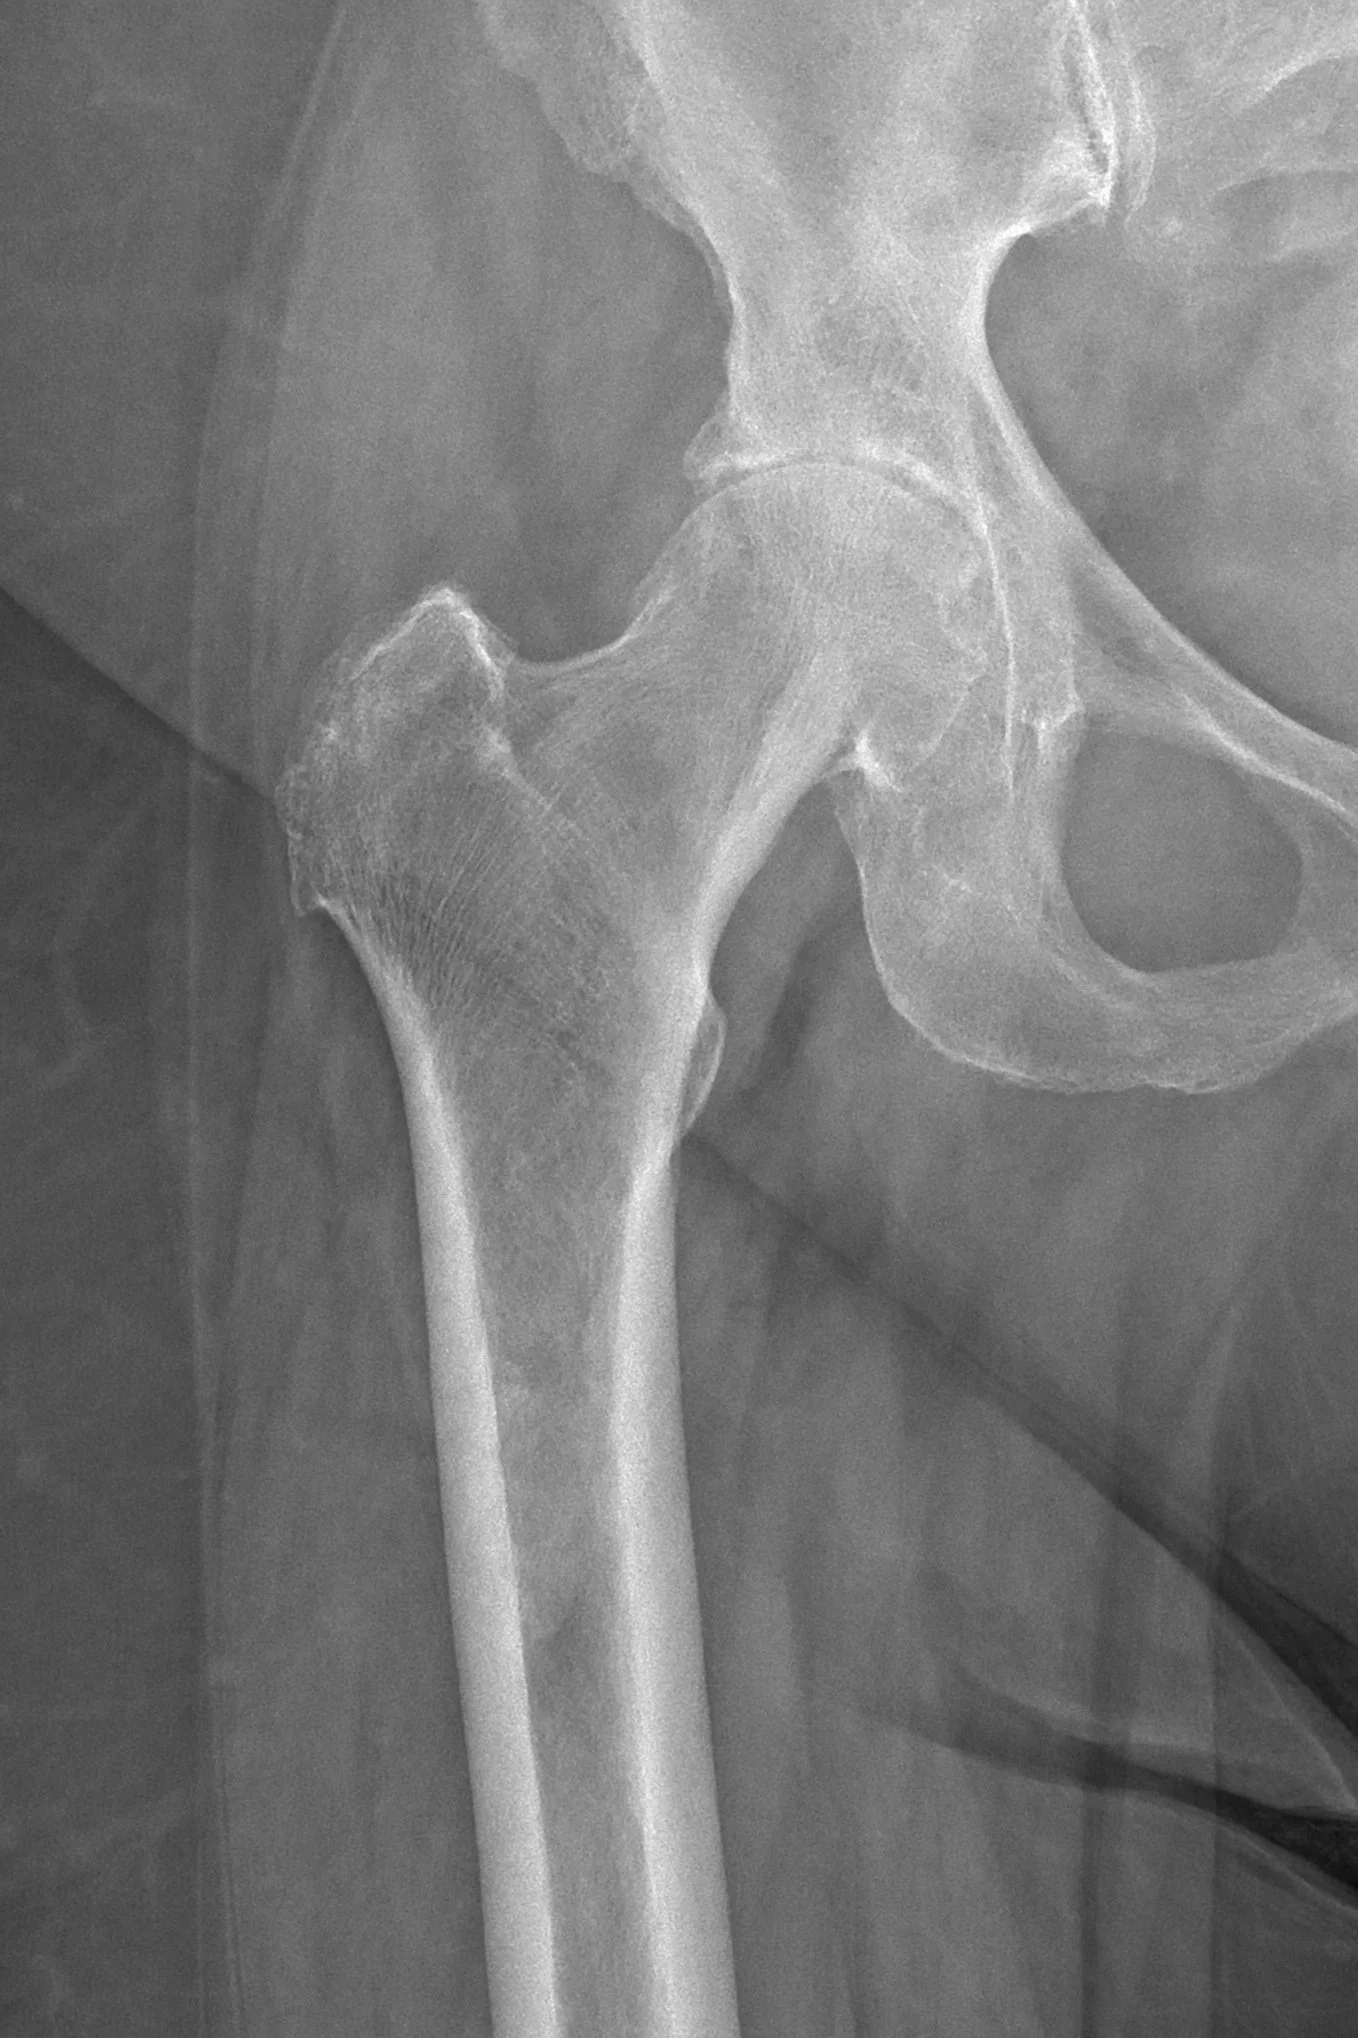

X-ray of hip joint with advanced arthritis prior to hip replacement surgery.

Before Surgery

Advanced degenerative arthritis

Preoperative X-rays often demonstrate joint space narrowing, bone-on-bone contact, osteophyte formation, and deformity related to advanced arthritis.